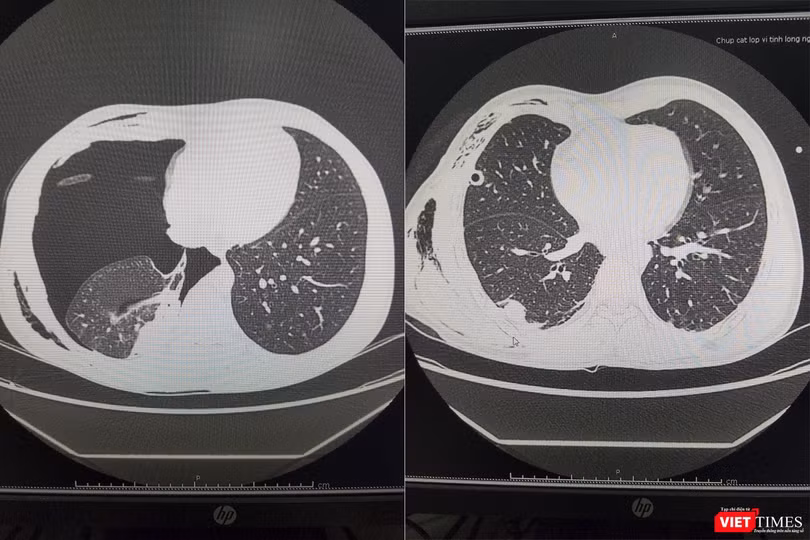

Sau 10 ngày phẫu thuật, bệnh nhân được dẫn lưu hút áp lực liên tục không ra khí, chụp lại cắt lớp vi tính lồng thấy ngực phổi nở tốt, không thấy dịch khí khoang màng phổi 2 bên. Người bệnh đã được ra viện sau đó 2 ngày.